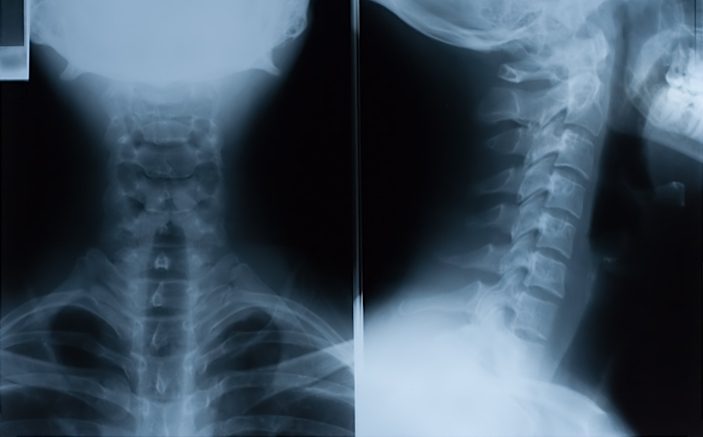

При установлении диагноза специалист учитывает историю болезни, осмотр пациента и результаты лабораторных исследований. На основе собранной информации чаще всего удается определить диагноз. Однако иногда требуются дополнительные исследования:

- общий анализ крови (ОАК);

- электромиография;

- рентгенография.